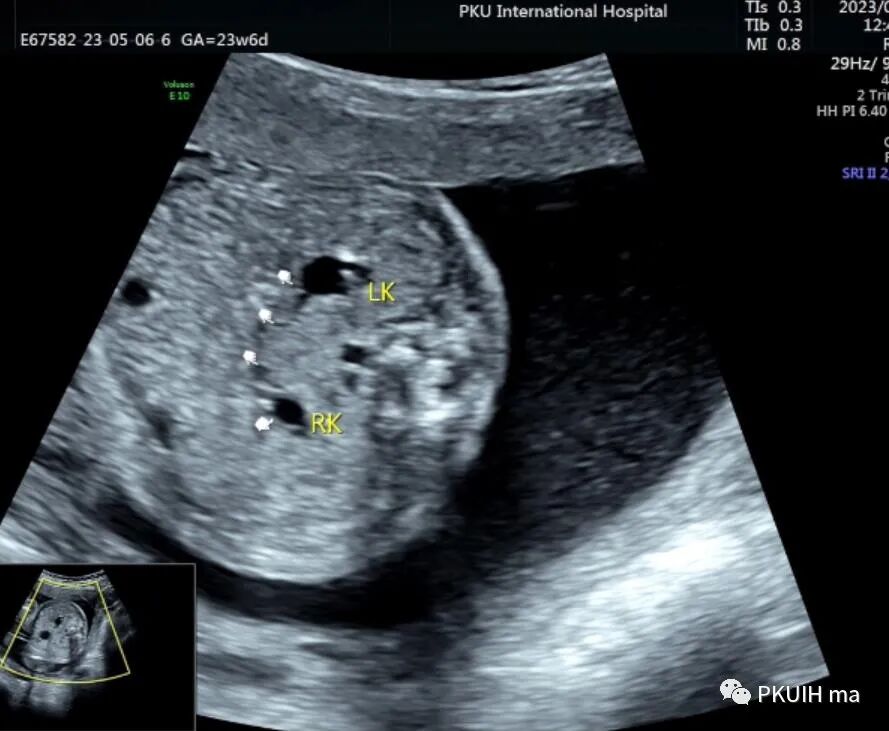

双肾横断面观察双肾盂轻微分离,肾门指向腹侧,呈倒“八”字征。(LK:左肾,RK:右肾)

仔细观察双肾下极越过腹主动脉于腹主动脉和下腔静脉的前方相融合,同时肾的位置相对低,下极接近胎儿膀胱。(DAO:降主动脉,IVC:下腔静脉,BL:膀胱)